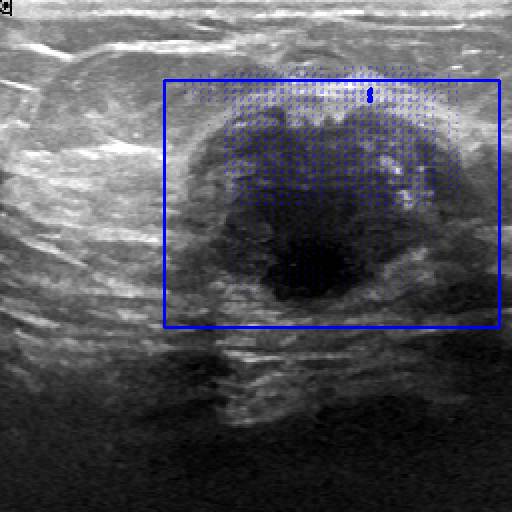

| Fine-Tuning | BUID [70] | 2D Ultrasound | 647 | Breast Cancer Segmentation | ||

| Method | ISIC-2018 (Skin Lesion) | JSRT (Lung X-ray) | KvaSir (Polyp) | Drive (Vessel) | BUID (Breast Cancer) | |

|---|---|---|---|---|---|---|

| Randomly (R50) | 86.16 0.14 | 93.10 0.12 | 62.85 1.32 | 59.82 2.00 | 65.54 0.21 | |

| Pre-trained ImageNet [60] | 86.87 0.47 | 94.52 2.66 | 83.85 1.32 | 65.12 1.55 | 72.64 1.14 | |

| Attention-Unet [77] | 86.81 0.51 | 94.47 2.71 | 82.23 1.41 | 65.02 1.44 | 72.19 1.16 | |

| U-Net ++ [78] | 86.71 0.49 | 94.32 2.81 | 82.23 1.41 | 65.38 0.78 | 73.76 2.83 | |

| 2D Supervised Method | Trans U-Net [76] | 86.60 0.82 | 89.80 0.35 | 67.11 0.24 | 62.63 0.24 | 67.90 0.40 |

| Twin-Barlon [13] | 86.01 0.07 | 94.56 3.09 | 83.00 0.23 | 65.73 1.46 | 74.46 1.19 | |

| Dino [79] | 86.79 0.09 | 94.84 2.79 | 79.84 1.62 | 65.39 0.81 | 76.21 0.57 | |

| SimCLR [15] | 87.28 0.21 | 94.79 2.93 | 82.20 0.51 | 65.22 2.18 | 76.52 0.22 | |

| Moco-v2 [17] | 87.24 0.14 | 94.05 3.52 | 78.24 1.35 | 64.92 2.21 | 75.93 1.96 | |

| Deepcluster-v2 [20] | 86.73 0.42 | 94.79 2.89 | 82.69 0.75 | 64.14 0.92 | 76.33 0.99 | |

| VicRegl [14] | 86.27 0.33 | 94.39 3.25 | 81.93 0.48 | 66.17 0.27 | 75.29 0.64 | |

| 2D-SSL on medical | LVM-Med (R50) | 87.76 0.30 | 95.13 2.64 | 86.76 0.94 | 66.97 0.27 | 78.65 0.72 |

| Clip [3] | 85.98 0.19 | 89.00 1.08 | 72.63 0.37 | 63.01 0.36 | 70.43 0.24 | |

| Flava [5] | 86.42 0.10 | 90.08 0.20 | 69.47 0.05 | 61.09 0.45 | 67.54 1.17 | |

| SAM [6] | 88.17 0.30 | 90.68 0.40 | 70.75 0.60 | 64.04 0.41 | 73.07 0.66 | |

| Foundation Model | LVM-Med (SAM’s ViT) | 88.41 0.28 | 90.74 0.47 | 73.10 0.08 | 65.49 0.12 | 77.20 0.42 |

| SAM (fixed encoder) [9] | 92.42 0.12 | 92.89 5.24 | 89.37 0.57 | 59.74 0.63 | 87.63 0.67 | |

| SAM with Prompt (no-train) [6] | 55.78 0.66 | 61.97 4.48 | 80.77 0.19 | 15.12 0.24 | 78.44 1.01 | |

| Prompt-based Seg. | LVM-Med (SAM’s ViT) | 92.48 0.07 | 93.74 4.06 | 90.09 0.14 | 63.01 0.02 | 89.69 0.61 |

In 3D settings, we segment 2D slices and merge results for a 3D volume. We also benchmarked with 3D self-supervised methods from [86]. Tables (2) and (3) show that our two versions with ResNet-50 and Sam’s ViT hold the best records in each category. For instance, we outperform 2D SSL methods trained on the same dataset, surpassing foundation models such as SAM, Flava, and Clip. In the prompt-based settings, LVM-Med also delivers better performance compared with SAM. Second, LVM-Med achieves the best overall results on seven of eight segmentation tasks, mostly held by LVM-Med with ResNet-50. The improvement gaps vary on each dataset, for e.g., from on Kvasir and BUID compared with 2D supervised methods.